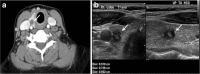

Focal and diffuse thyroid abnormalities are commonly encountered during the interpretation of computed tomography (CT) exams performed for various clinical purposes. These findings can often lead to a diagnostic dilemma, as the CT reflects the nonspecific appearances. Ultrasound (US) examination has a superior spatial resolution and is considered the modality of choice for thyroid evaluation. Nevertheless, CT detects incidental thyroid nodules (ITNs) and plays an important role in the evaluation of thyroid cancer. In this pictorial review, we cover a wide spectrum of common and uncommon, incidental and non-incidental thyroid findings from CT scans. We also discuss the most common incidental thyroid findings, best practices for their evaluation, and recommendations for their management. In addition, we explore the role of imaging in the assessment of thyroid carcinoma (before and after treatment) and preoperative thyroid goiter, as well as localization of ectopic and congenital thyroid tissue.